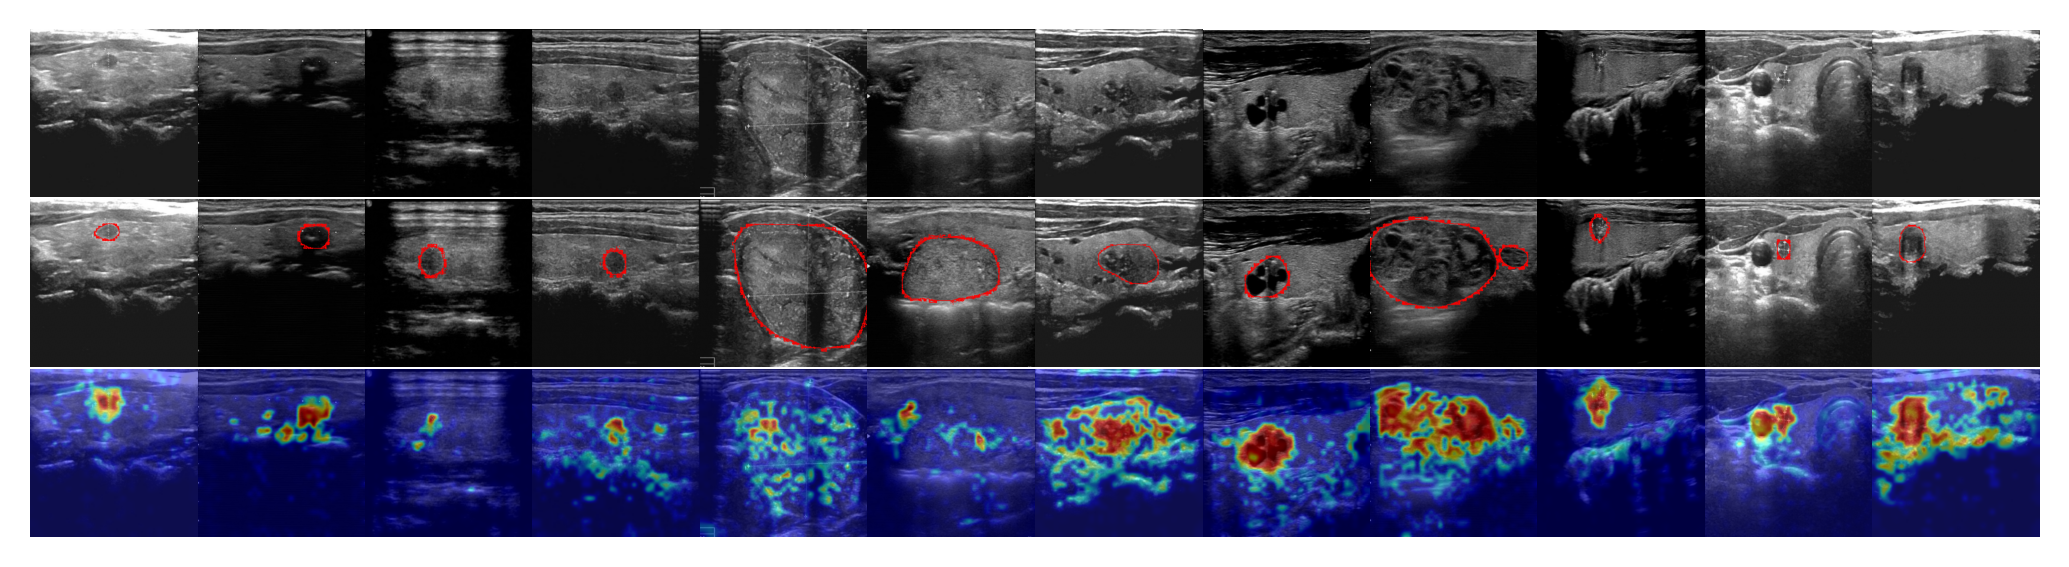

Anomaly detection (AD) has been widely applied in various applications, such as industrial defect inspection (bergmann2019mvtec; xie2023pushing; roth2022towards; huang2022registration; mou2022rgi; chen2022deep; bergmann2020uninformed; pang2021explainable; reiss2023mean; you2022unified; liznerski2020explainable; ding2022catching; 9940966; cao2023anomaly) and medical image analysis (pang2021explainable; qin2022medical; liu2023clip; ding2022catching; tian2021constrained; tian2023self; fernando2021deep). Existing AD approaches typically assume that training examples in a target application domain are available for learning the detection models (pang2021deep; ruff2021unifying). However, this assumption may not hold in various scenarios, such as i) when accessing training data violates data privacy policies (e.g., to protect the sensitive information of patients), or ii) when the target domain does not have relevant training data (e.g., inspecting defects in a manufacturing line of new products). Zero-shot anomaly detection (ZSAD) is an emerging task for AD in such scenarios, to which the aforementioned AD approaches are not viable, as it requires detection models to detect anomalies without any training sample in a target dataset. Since anomalies from different application scenarios typically have substantial variations in their visual appearance, foreground objects, and background features, e.g., defects on the surface of one product vs. that on the other products, lesions/tumors on different organs, or industrial defects vs. tumors/lesions in medical images, detection models with strong generalization ability w.r.t. such variations are needed for accurate ZSAD. Recently large pre-trained vision-language models (VLMs) (radford2021learning; kirillov2023segment) have demonstrated strong zero-shot recognition ability in various vision tasks, including anomaly detection (jeong2023winclip). Particularly, being pre-trained using millions/billions of image-text pairs, CLIP (radford2021learning) has been applied to empower various downstream tasks (zhou2022learning; rao2022denseclip; khattak2023maple; sain2023clip) with its strong generalization capability. WinCLIP (jeong2023winclip) is a seminal work in the ZSAD line, which designs a large number of artificial text prompts to exploit the CLIP’s generalizability for ZSAD. However, the VLMs such as CLIP are primarily trained to align with the class semantics of foreground objects rather than the abnormality/normality in the images, and as a result, their generalization in understanding the visual abnormality/normality is restricted, leading to weak ZSAD performance. Further, the current prompting approaches, using either manually defined text prompts (jeong2023winclip) or learnable prompts (sun2022dualcoop; zhou2022conditional), often result in prompt embeddings that opt for global features for effective object semantic alignment (zhong2022regionclip; wu2023aligning), failing to capture the abnormality that often manifests in fine-grained, local features, as shown in Fig. 1d and Fig. 1e. In this paper we introduce a novel approach, namely AnomalyCLIP, to adapt CLIP for accurate ZSAD across different domains. AnomalyCLIP aims to learn object-agnostic text prompts that capture generic normality and abnormality in an image regardless of its foreground objects. It first devises a simple yet universally-effective learnable prompt template for the two general classes – normality and abnormality – and then utilizes both image-level and pixel-level loss functions to learn the generic normality and abnormality globally and locally in our prompt embeddings using auxiliary data. This allows our model to focus on the abnormal image regions rather the object semantics, enabling remarkable zero-shot capability of recognizing the abnormality that has similar abnormal patterns to those in auxiliary data. As shown in Fig. 1a and Fig. 1b, the foreground object semantics can be completely different in the fine-tuning auxiliary data and target data, but the anomaly patterns remain similar, e.g., scratches on metal nuts and plates, the misplacement of transistors and PCB, tumors/lesions on various organ surfaces, etc. Text prompt embeddings in CLIP fail to generalize across different domains, as illustrated in Fig. 1c, but object-agnostic prompt embeddings learned by AnomalyCLIP can effectively generalize to recognize the abnormality across different domain images in Fig. 1f.

Figure 1: Comparison of ZSAD results on (b) test data using (c) original text prompts in CLIP (radford2021learning), (d) tailored text prompts for AD in WinCLIP (jeong2023winclip), (e) learnable text prompts for general vision tasks in CoOp (zhou2022conditional), and (f) object-agnostic text prompts in our AnomalyCLIP. (a) presents a set of auxiliary data we can use to learn the text prompts. The results are obtained by measuring the similarity between text prompt embeddings and image embeddings. The ground-truth anomaly regions are circled in red in (a) and (b). (c), (d), and (e) suffer from poor generalization across different domains, while our AnomalyCLIP in (f) can well generalize to anomalies in diverse types of objects from different domains.

Table 1 shows the ZSAD results of AnomalyCLIP with five competing methods over seven industrial defect datasets of very different foreground objects, background, and/or anomaly types. AnomalyCLIP achieves superior ZSAD performance across the datasets, substantially outperforming the other five methods in most datasets. The weak performance of CLIP and CLIP-AC can be attributed to CLIP’s original pre-training, which focuses on aligning object semantics rather than anomaly semantics. By using manually defined text prompts, WinCLIP and VAND achieve better results. Alternatively, CoOp adopts learnable prompts to learn the global anomaly semantics. However, those prompts focus on the global feature and ignore the fine-grained local anomaly semantics, leading to their poor performance on anomaly segmentation. To adapt CLIP to ZSAD, AnomalyCLIP learns object-agnostic text prompts to focus on learning the generic abnormality/normality using global and local context optimization, enabling the modeling of both global and local abnormality/normality. Our resulting prompts can also generalize to different datasets from various domains. To provide more intuitive results, we visualize the anomaly segmentation results of AnomalyCLIP, VAND, and WinCLIP across different datasets in Fig. 4. Compared to VAND and WinCLIP, AnomalyCLIP can perform much more accurate segmentation for the defects from different industrial inspection domains.

Generalization from defect datasets to diverse medical domain datasets

To evaluate the generalization ability of our model, we further examine the ZSAD performance of AnomalyCLIP on 10 medical image datasets of different organs across different imaging devices. Table 2 shows the results, where learning-based methods, including AnomalyCLIP, VAND and CoOp, are all tuned using MVTec AD data. It is remarkable that methods like AnomalyCLIP and VAND obtain promising ZSAD performance on various medical image datasets, even though they are tuned using a defect detection dataset. Among all these methods, AnomalyCLIP is the best performer due to its strong generalization brought by object-agnostic prompt learning. As illustrated in Fig. 4, AnomalyCLIP can accurately detect various types of anomalies in diverse medical images, such as skin cancer regions in photography images, colon polyps in endoscopy images, thyroid nodules in ultrasound images, and brain tumors in MRI images, having substantially better performance in locating the abnormal lesion/tumor regions than the other two methods WinCLIP and VAND. This again demonstrates the superior ZSAD performance of AnomalyCLIP in datasets of highly diverse object semantics from medical imaging domains.